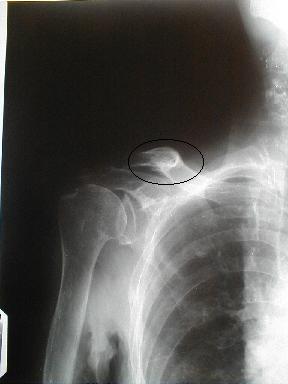

症例6

右鎖骨骨折

86歳 女性

負傷年日 平成10年10月11日

負傷原因 自宅の物干し場で上を見上げて洗濯物を干していてフラフラとなり、転倒負傷

10月24日受傷13日目

当初さほどに痛みを感じなかったので我慢していたが、徐々に肩に違和感を訴え我慢できず来院レントゲン検査したところ骨折を認める

皮下溢血,腫脹,圧痛